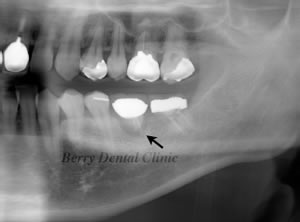

移植から2年後のお写真です。

矢印の部分に少し拒絶反応が認められますが、患者さんは痛くなく腫れもないので問題なく食事ができるという事でそのまま様子を見ています。

移植からさらに7年後のお写真ですが、ほとんど変わりなく患者さんの状態もとてもいいのでこのままさらに状態をみているところです。

矢印の歯は完全に安定しています。